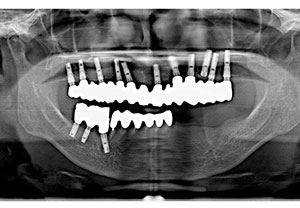

16年後のレントゲン写真

| 治療内容 | 主訴:強度の嘔吐反応があり、義歯を入れる事が出来ないため、当院へご相談しに来院されました。 処置:重度の歯周病のため、上顎は全て歯を抜歯して、10本のインプラント治療を、科学は歯周外科手術を行った後に3本のインプラント埋入して噛めるようにする治療計画を立てました。上顎両側の骨幅が足りないので、スプリットクレスト法(歯槽骨頂分割術)を用いて、インプラント(人工歯根)を埋める一次手術を行いました。その後、上顎の二次手術と下顎右側臼歯部の人工歯根を埋める一次手術を同時に行いました。義歯を入れる事が出来なかった患者様でしたが、「ちゃんと噛めて夢のようです。」と感動されました。定期的にメンテナンスにもこられ、16年後も全てインプラントが安定されております。 |

| 費用 | 総額 4,141,500円(税込) ・インプラント様(片顎)CT撮影 11,000円(税込) ・静脈内鎮静法B(ドルミカム) 27,500円(税込) ・フェクスチャー(インプラント) 242,000円×10本=2,420,000円(税込) ・セラミック冠(冠+アパットメント) 143,000円×10本=1,430,000円(税込) ・ポンテック 143,000円×2本=286,000円(税込) |